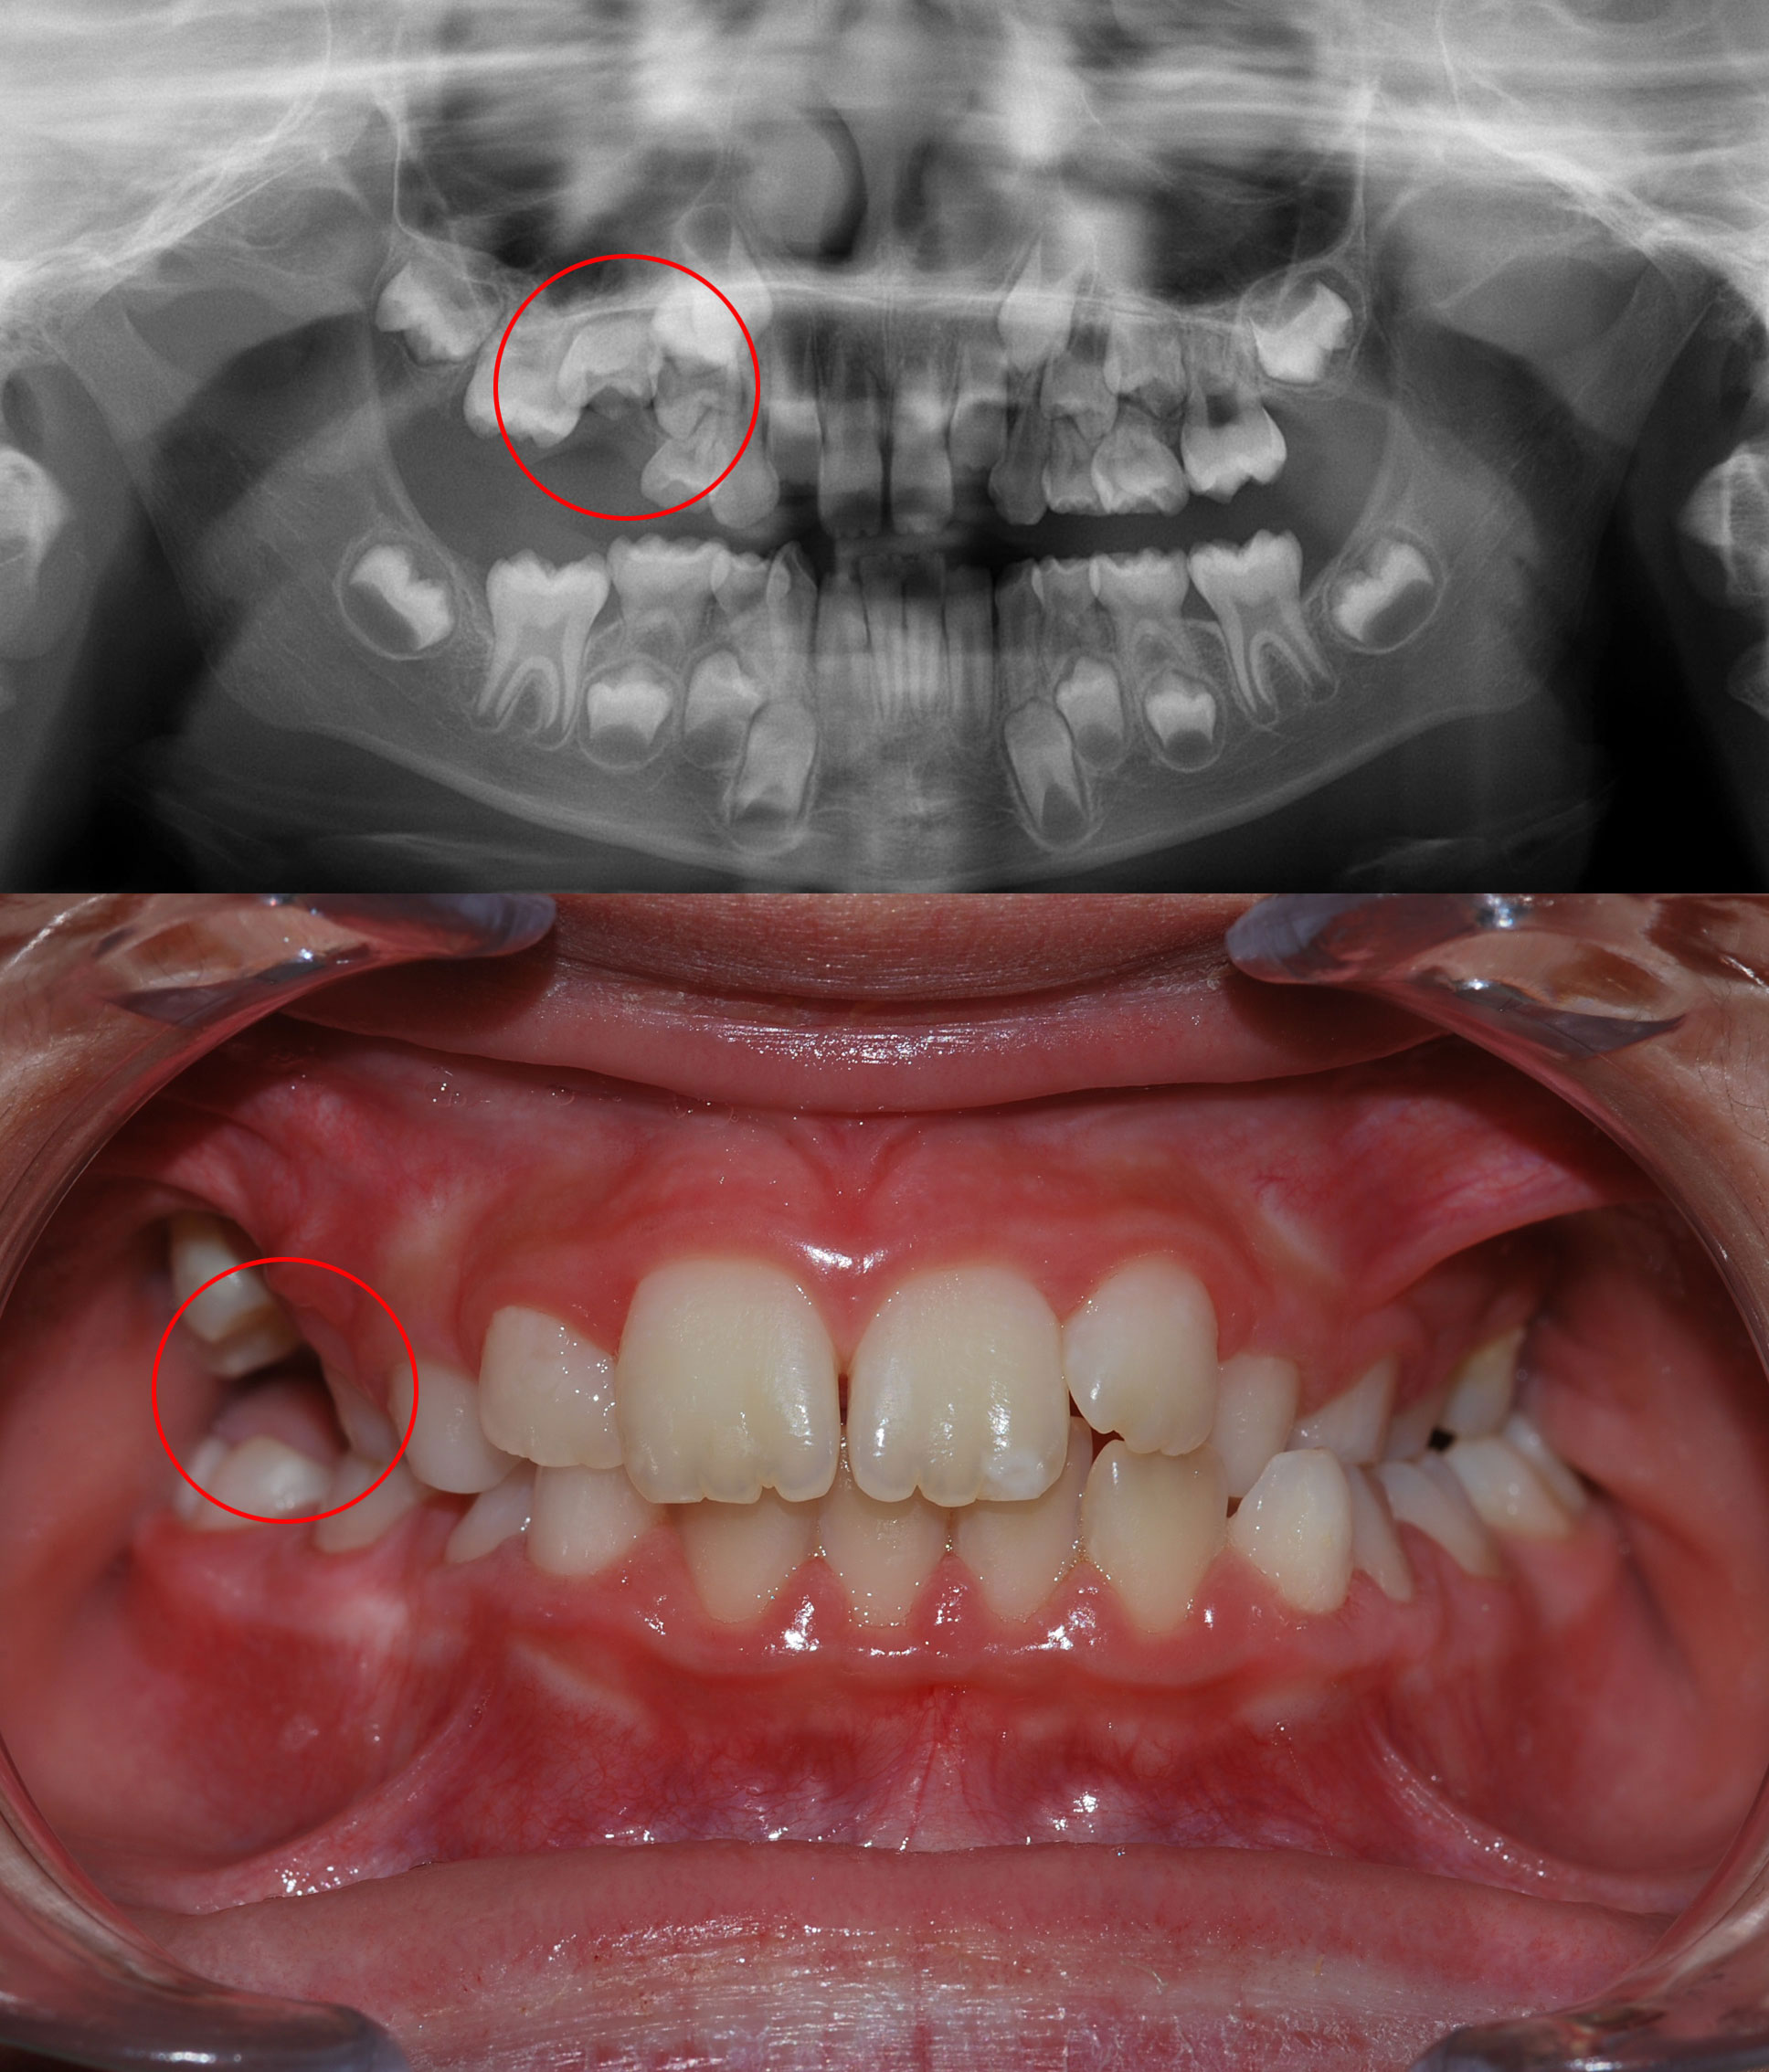

Problemas Eruptivos

En ocasiones uno o más dientes erupcionan muy alejados de su sitio correcto en la arcada dentaria (diente ectópico) o no erupcionan y se quedan dentro del hueso (diente incluido o transposición). Son problemas complejos y su abordaje precoz mejora enormemente el pronóstico.